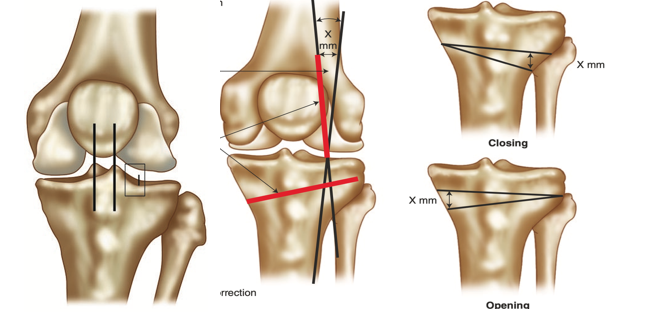

By realigning the mechanical axis of the lower limb, HTO unloads the damaged medial compartment and can restore more physiological joint mechanics (Murray, Winkler, Shaikh, & Musahl, 2021). The procedure is most commonly performed as a medial opening-wedge osteotomy, where a controlled cut is made in the upper tibia and opened to the desired correction angle.